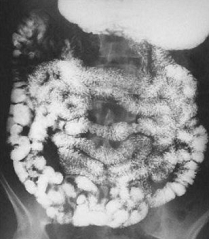

Рентгеноскопия верхних отделов пищеварительного

тракта

Рентгенография верхних отделов ЖКТ представляет

собой рентгенологическое исследование глотки, пищевода, желудка и начальных

отделов тонкого кишечника (двенадцатиперстной кишки). Для получения изображений

используется особая разновидность исследования под названием флюороскопия и

вводимый перорально (через рот) контрастный материал в виде бария.

Рентгенография глотки Рентгенография пищевода

Рентгенография желудка Контрастная

рентгенография тонкого … кишечника

тракта (глотки, пищевода, желудка и двенадцатиперстной кишки) до настоящего

времени остается одним из основных методов диагностики злокачественных

новообразований этих органов. В современной рентгенодиагностике все четыре

перечисленных органа исследуются одновременно. Особое значение имеет

возможность обнаружения опухолей, обладающих интрамуральным (внутри стенки) или

экзоорганным (кнаружи от стенки органа) ростом, а также новообразований

соседних органов, которые не видны при эндоскопических исследованиях.